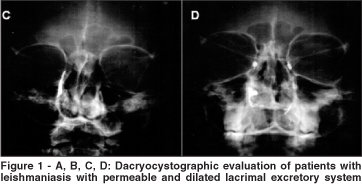

All patients who presented an abnormal Jones I test were submitted to dacryocystography and nasal endoscopy evaluation. The main alteration observed in the dacryocystographic examination was nasolacrimal duct dilation which was completely permeable to the contrast (Figure 1 A, B, C, D).

The nasolacrimal duct dilation was bilateral in 11 patients (22 nasolacrimal ducts) and unilateral in two (2 nasolacrimal ducts). Thus the dilated and permeable ducts were observed in 92.30% (24/26) of the lacrimal excretory systems evaluated by dacryocystography. The lacrimal sac was dilated in one patient (3.84% - 1/26) (Figure 2) and another (3.84% - 1/26) presented a nasolacrimal duct obstruction.

The dacryocystographic examination consisted of dilation of the inferior lacrimal punctum using a lacrimal punctum dilator and injection of an oily radiographic contrast material (Lipiodol - Guerbet) via a cannula into the inferior canaliculus of the lacrimal drainage system. The patient was then submitted to an X-Ray which allowed us to observe good opacification of the superior, inferior, common canalicui and nasolacrimal ducts at the medial aspect of the orbit in the anterior-posterior view. Contrast could normally be seen exteriorizing into the inferior meatus where the ducts empty(15).